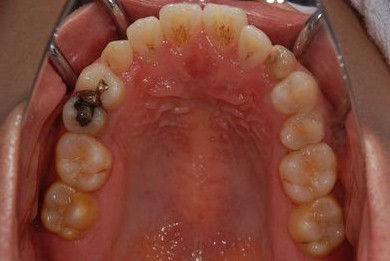

治療後

• 治療後